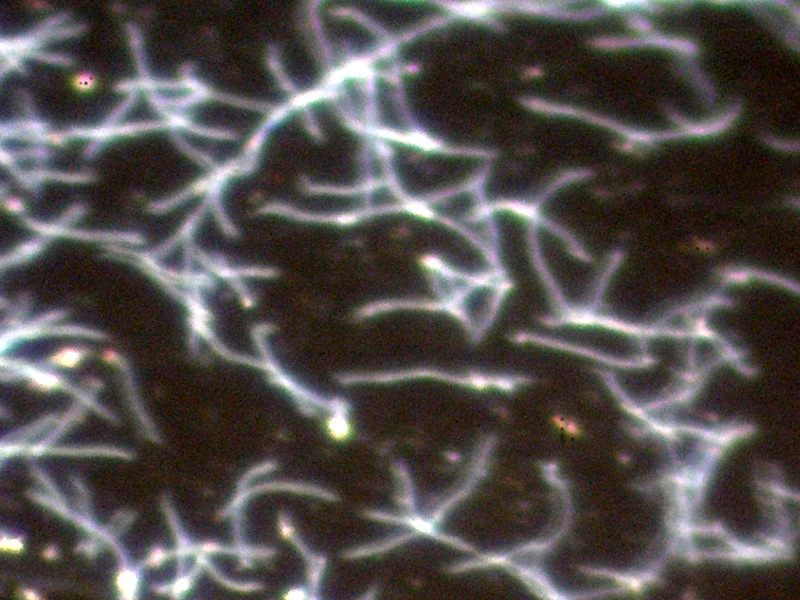

Als Standardmethode zur Diagnose der Leptospirose dient der Nachweis der von infizierten Menschen oder Tieren gebildeten Antikörper mittels Mikroagglutinationstest (MAT). Bei dem MAT werden die Seren der Patienten verdünnt und mit lebenden Leptospirenstämmen versetzt; beim Vorhandensein von Antikörpern kommt es zu Reaktionen (Verklumpungen) der Leptospiren, die mikroskopisch beurteilt werden (siehe Abbildungen).

Lebende Leptospiren im Dunkelfeldmikroskop (Vergrößerung 1:500)